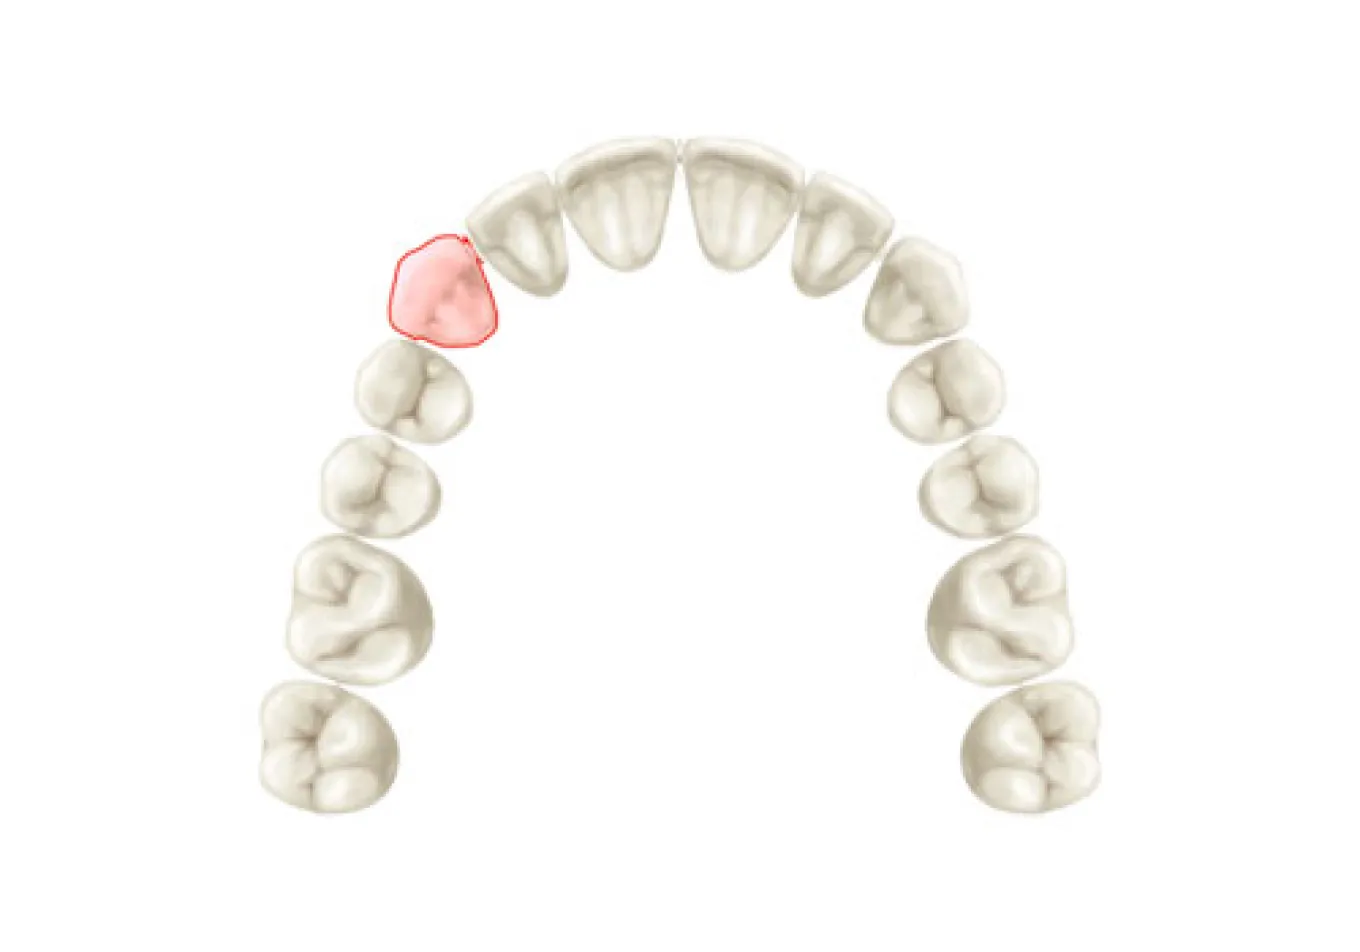

インプラント(implant)とは、“植え込む”という意味の英語です。インプラントの仕組みは、歯を失ってポッカリ穴が開いてしまった部分の歯龎骨へ穴を開け、インプラント体(フィクスチャー)と呼ばれる金属製の人工歯根(インプラント体)を埋め込み、その上に人工の歯を被せるしくみです。 歯龎の骨にしっかりとインプラント体を固定する事により、浮かない・ずれない・しっかりとした噛み心地を実現する事が出来ます。 人は永久歯を失うと、残念ながら二度と生え変わってきません。そのため、今までは『義歯(入れ歯)』『ブリッジ』などを用いて食事や会話 を取り戻すといった方法でしか、その部分を補う事はできませんでした。 しかし、『義歯(入れ歯)』だと固いものがうまく噛めない、発音がおかしい、また長く使っている間に合わなくなってガタガタする場合があります。 このように、歯を失ってお悩みの方にご提供することができる、最新歯科医療の治療方法『インプラント治療(人工歯根)」です。 歯を抜けたままにして放置しておくと、お口の中には様々な影響が出てきます。奥歯の下の歯が1本抜けた場合、まずこれまでその歯と噛み合っていた上の歯が下に伸びてきます。また、両隣の歯が抜けた歯の方向に倒れてきて、さらにはそこにプラークがたまりやすくなってしまいます。結果として、虫歯や歯周病などが誤発されることがあります。歯はかなり緬密に全体のバランスの中で成り立っているものなので、例え1本の欠損の場合でも、そのままにしておくことはお勧めできません。 機能的な影響 見た目上の影響 生活上の影響 取り外す入れ歯が嫌な方、取り外す入れ歯の清掃が面倒くさいと感じる方 入れ歯は食事のたびにお口から取って清掃しなくてはなりません。清掃が不十分だと歯周病の原因となります。お悩みの方は一度、ご相談下さい。 入れ歯が合わない方、何度も入れ歯をつくり直している方 入れ歯は歯肉を圧迫するので、歯肉がやせていきます。歯肉がやせると入れ歯との間に隙間ができ、密着しにくくなりお食事中などに外れる場合があります。 入れ歯で発音しにくい(話しにくい)方 入れ歯を使い始めてすぐは、発音のしづらさを感じます。人前で話す機会の多い方や英語を話す方は入れ歯により発音が悪くなります。特に、 楽器の演奏をされる方で前歯を失った場合には、インプラント治療が非常にお勧めです。 思いっきり笑ったり、歯を見せて話ができない方、入れ歯のバネが気になっている方 会話や食事の際など、お口をあけた時に入れ歯のバネが見えてしまう場合があります。入れ歯のバネが気になっている方は当院にご相談下さい。 口臭が気になる方 最近、口臭が原因で来院される患者様が増えています。実際に当院では口臭があると診断された患者様のほとんどの方が歯周病に侵されます。歯周病に侵され、残念ながら歯を失うことになった場合には、インプラント治療を勧められることがあります。 昔食べられていたものが噛めない方、左右片方でしかものが噛めない方 入れ歯は天然歯の1/3程度しか噛む力がありません。総入れ歯の場合は硬いものを噛むときに痛みを覚えます。昔の「歯」のようにしっかり噛 んで食事をしたいとお考えの方は一度、ご相談下さい。 自分の歯のように見た目をきれいにしたい方 インプラントは、天然歯とほとんどかわらない「機能性」「審美性」をもっています。自分の歯のように見た目を綺麗にしたいとお考えの方 は一度お問い合わせください。 健康な歯は、これからもできる限り残したい方 インプラント治療なら、隣の歯(まわりの健康な歯)を傷つけることなく欠損した歯だけを治療することが可能です。健康な歯を出来るだけ 残したいとお考えの方は当院までお問い合わせください。 旅行やスポーツを積極的に楽しみたい方 旅行先での美味しいものを存分に味わいたい、スポーツをする際、歯に力を入れたい、積極的に楽しみたいとお考えの方には、インプラント 治療がお勧めです。一度、当院にお問い合わせください。一つでもチェックした方はまず、当院へご相談下さい。 しっかりと噛める インプラントはあごの骨の中に埋め込まれ、しっかりと固定されますので、入れ歯とは違い、しっかりとした噛み心地が得られるのが大きな魅力です。しっかりと噛めるというのは、消化の面で良いのはもちろんですが、その他にも認知症の予防や、体の運動能力の向上にも役立つことがわかっており、若々しさを保つ上でも役立ちます。 見た目が自然 インプラントは人工歯根をあごの骨に埋め込み、その上に被せ物をする治療ですが、実際に表から見える部分というのは被せ物の部分だけです。被せ物は主に周囲の歯に似せたセラミックを入れますので、まるでご自分の歯のように見えます。 違和感がなく快適 インプラントの人工歯根は骨と結合して一体化し、まるで体の一部のような感じになります。一方、取り外し式の入れ歯の場合、歯茎の上に乗っているため、違和感に悩まされる方も少なくありません。 残った歯を長持ちさせてくれる インプラントは、単独で歯を立てられる治療法ですので、他の治療法と違い、周囲の歯にダメージを与えることがありません。例えばブリッジの場合、失った歯の両隣の歯をたくさん削って被せなければなりませんし、入れ歯の場合だと、残っている歯に金具をかけて入れ歯を支えなければなりません。このような周囲の歯へのダメージが徐々に歯を弱らせてしまうことにつながっていき、最終的には歯の寿命を短くしてしまいます。単独で歯をおぎなうことのできるインプラントは、歯を全体的に健康に保ってくれる治療法だと言えるでしょう。 お手入れが楽 インプラントは、基本的にご自分の歯を磨くようにお手入れをします。一方、入れ歯の場合は取り外して入れ歯とご自分の歯を別々に磨く必要がありますし、ブリッジの場合には、つなぎの部分などの形が複雑で、隅々まで磨くのが大変です。 あごの骨がやせにくい インプラントとあごの骨はしっかりと結合していますので、噛んだ刺激は直接骨に伝わります。あごの骨というのは噛む刺激を受けないとだんだんやせてしまいます。そのため、入れ歯やブリッジの場合には徐々に骨がやせていきます。インプラントの場合には常に噛む刺激が伝わるため、骨の高さが維持されてお顔の張りも保たれることになり、若々しい見た目を維持することができます。 保険適用にならない 通常、インプラントは保険が適用されません。そのため、治療費は100%自己負担となりますので高額になってしまいます。 手術を受けなければならない インプラントは人工歯根をあごの骨に埋める手術が必要です。手術の侵襲の程度は抜歯程度のものが多いですが、やはり外科的な処置が必要になります。 治療期間が長くかかる インプラントは他の治療法に比べて治療期間が長くかかります。それはインプラントがあごの骨と結合するまでじっくりと待たなければならないためです。通常、下あごの場合3ヶ月程度、上あごの場合6ヶ月程度ほど治療期間がかかりますが、骨が少ない場合には骨を作る治療が必要となりますので、さらに数ヶ月かかることもあります。 全身状態、骨の状態などによっては治療不可 糖尿病や高血圧がしっかりとコントロールされていない場合など、全身状態によっては手術が行えない場合があります。また、インプラントを埋める部分の骨の状態が良くない場合には行えない場合があります。 メンテナンスを怠ると抜け落ちることがある メンテナンスは、どの治療法にとっても長く持たせるためには必要不可欠ですが、インプラントの場合、毎日のお手入れや、歯科医院での定期的なメンテナンスを怠ると細菌感染を起こし、ご自分の歯と同様、抜け落ちてしまうことがあります。特にタバコを吸う場合、インプラント周囲の組織が感染を起こしやすくなるため、より注意が必要です。 失った部分にインプラントを1本埋入します。 従来は部分的な入れ歯を用いて治療を行っていましたが、インプラントを何本か用いて治療を行います。入れ歯を固定するための金属のバネによる違和感がなくなります。 従来の総入れ歯ではなくインプラントを用いて治療します。この方法なら食物が入れ歯と歯茎の間にはさまったり、入れ歯が合わなくなるようなことはありません。 LMGでは実際に当院で行ったインプラント手術の症例を公開しております。歯を失ってしまった方や、歯周病等で歯を残すことが困難と診断された方は当院でのインプラント治療なら綺麗で咬みやすい口腔内を取り戻すことができるかもしれません。ぜひチェックしてみてください。 あらゆる治療に言えることですが、インプラント治療は思い立ってすぐに取り掛かれる治療ではありません。インプラントはあごの骨を削る治療も必要ですので、安全に治療を進めていく上でも、治療を開始するにあたって十分な検査や前準備が必要となります。 インプラントはあごの骨を削る治療も必要ですので、安全に治療を進めていく上でも、治療を開始するにあたって十分な検査や前準備が必要となります。 インプラント治療についてあまりよく知らない、という方も多いと思います。 そのため、患者様がすでにインプラントをご希望されている場合でも、まずは十分なカウンセリングを行ない、ご理解を深めていただいた上で治療を進 めていくことになります。 患者様の歯のお悩み、ご希望をお聞きした上で、インプラント治療についての 説明を行います。インプラント治療の治療の進め方、どのような手術になるの か、リスク、期間、費用、またインプラント治療のメリットだけでなくデメ リットに関しても詳しくお話しいたします。 院では、患者様に十分にインプラント治療をご理解いただき、ご納得いただ いた上でインプラント治療を開始するようにしています。不安な点、疑問な点 などはどんなことでもためらわずにお話しください。 もちろんインプラント以外の可能な治療法に関しても、すべてメリット、デメ リットも含めてご説明し、患者様ご自身に合った方法をお選びいただきます。 インプラントを行うためには、お口の状態の検査をしっかりと行う必要があります。それは他の治療に関しても同じことが言えるのですが、インプラントの 場合には特に、あごの骨の適切な位置にインプラントを狂いなく埋め込む必要があります。 それゆえ、安全に手術を行うためには、通常のレントゲンだけでなく、CT撮影も行なった上で、骨の状態や神経や血管の位置まで詳しく診査を行う必要があります。また、インプラントをベストな状態で行うためにも、お口の健康状態、かみ合わせの状態などもチェックしておきます。 検査結果をもとに、治療計画を綿密に立てていきます。患者様にベストと思われる治療計画をわかりやすくご説明し、ご納得いただければ治療開始となりま す。ただし、場合によってはすぐにインプラント治療が開始できない場合もあります。 たとえば大きな虫歯や、重度の歯周病がある場合、体の健康状態に問題がある場合などです。このような場合には、まずインプラントが健全な状態で行えるよう、問題点を解決してからインプラント治療に移行していきます。 手術の大まかな流れを説明します。手術の方法やインプラントの本数によって手術の計画は変更となります。 01 埋入手術 麻酔を行なった後、インプラントをあごの骨に埋め込んでいきます。多くの場合、抜歯程度の手術になりますので、通常の歯科の麻酔で問題なく手術が行えます。約3〜6ヶ月ほどの治癒期間を待ちます。 02 頭出し手術 インプラント手術を二回法で行なった場合に行われる簡単な手術です。歯茎で覆われていたインプラントの上部を露出させ、1〜2週間以上経ってから被せ物の型取りを行います。 03 被せ物の装着 出来上がった被せ物を装着します。 04 メインテナンス 長期的に良い状態でインプラントを保ち続けるために、定期的に通っていただきメインテナンスをお受けください。 インプラントは生体に埋め込む治療ですので、治癒期間などが必要となり、どうしても他の治療に比べて期間がかかってしまいます。そのため、インプラント手術を開始してから被せ物が最終的に入るまでに、3〜6ヶ月くらいはかかります。 この期間は骨の状態や手術の方法によって変わってきます。また、インプラント治療を開始する前に虫歯や歯周病の治療が必要な場合にはさらに期間がかかる場合もあります。 LMGでは実際に当院で行ったインプラント手術の症例を公開しております。歯を失ってしまった方や、歯周病等で歯を残すことが困難と診断された方は当院でのインプラント治療なら綺麗で咬みやすい口腔内を取り戻すことができるかもしれません。ぜひチェックしてみてください。しっかりとした噛み心地を実現する治療

精密検査